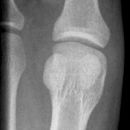

D1 Grundglied